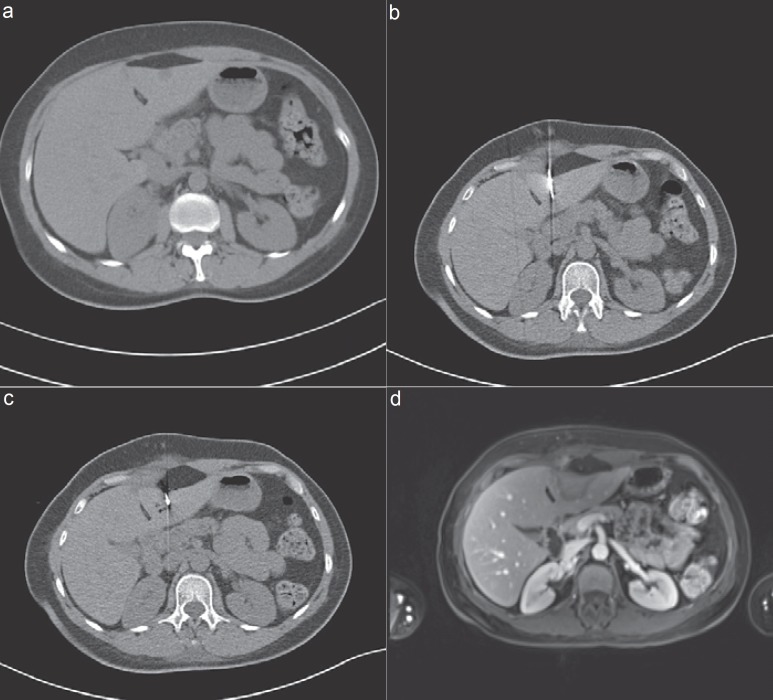

Methods: Liver-directed therapies are classified into vascular transarterial techniques such as chemoperfusion (TACP), chemoembolization (TACE), radioembolization (selective internal radiation therapy (SIRT)), and chemosaturation, as well as thermal ablation techniques like microwave ablation (MWA), radiofrequency ablation (RFA), laser-induced thermotherapy (LITT), cryotherapy, and irreversible electroporation (IRE). The authors searched the database PubMed using the following terms: 'image-guided tumor ablation', 'thermal ablation therapies', 'liver metastases of uveal melanoma', 'neuroendocrine carcinoma', 'breast cancer', and 'non-colorectal liver metastases'.

Results: Various combinations of the above-mentioned therapy protocols are possible. In neuroendocrine carcinomas, oligonodular liver metastases are treated successfully via thermal ablation like RFA, LITT, or MWA, and diffuse involvement via TACE or SIRT. Although liver involvement in breast cancer is a systemic disease, non-responding nodular metastases can be controlled via RFA or LITT. In ocular or cutaneous melanoma, thermal ablation is rarely considered as an interventional treatment option, as opposed to TACE, SIRT, or chemosaturation. Rarely liver-directed therapies are used in pancreatic cancer, most likely due to problems such as biliary digestive communications after surgery and the risk of infections. Rare indications for thermal ablation are liver metastases of other primary cancers like non-small cell lung, gastric, and ovarian cancer.